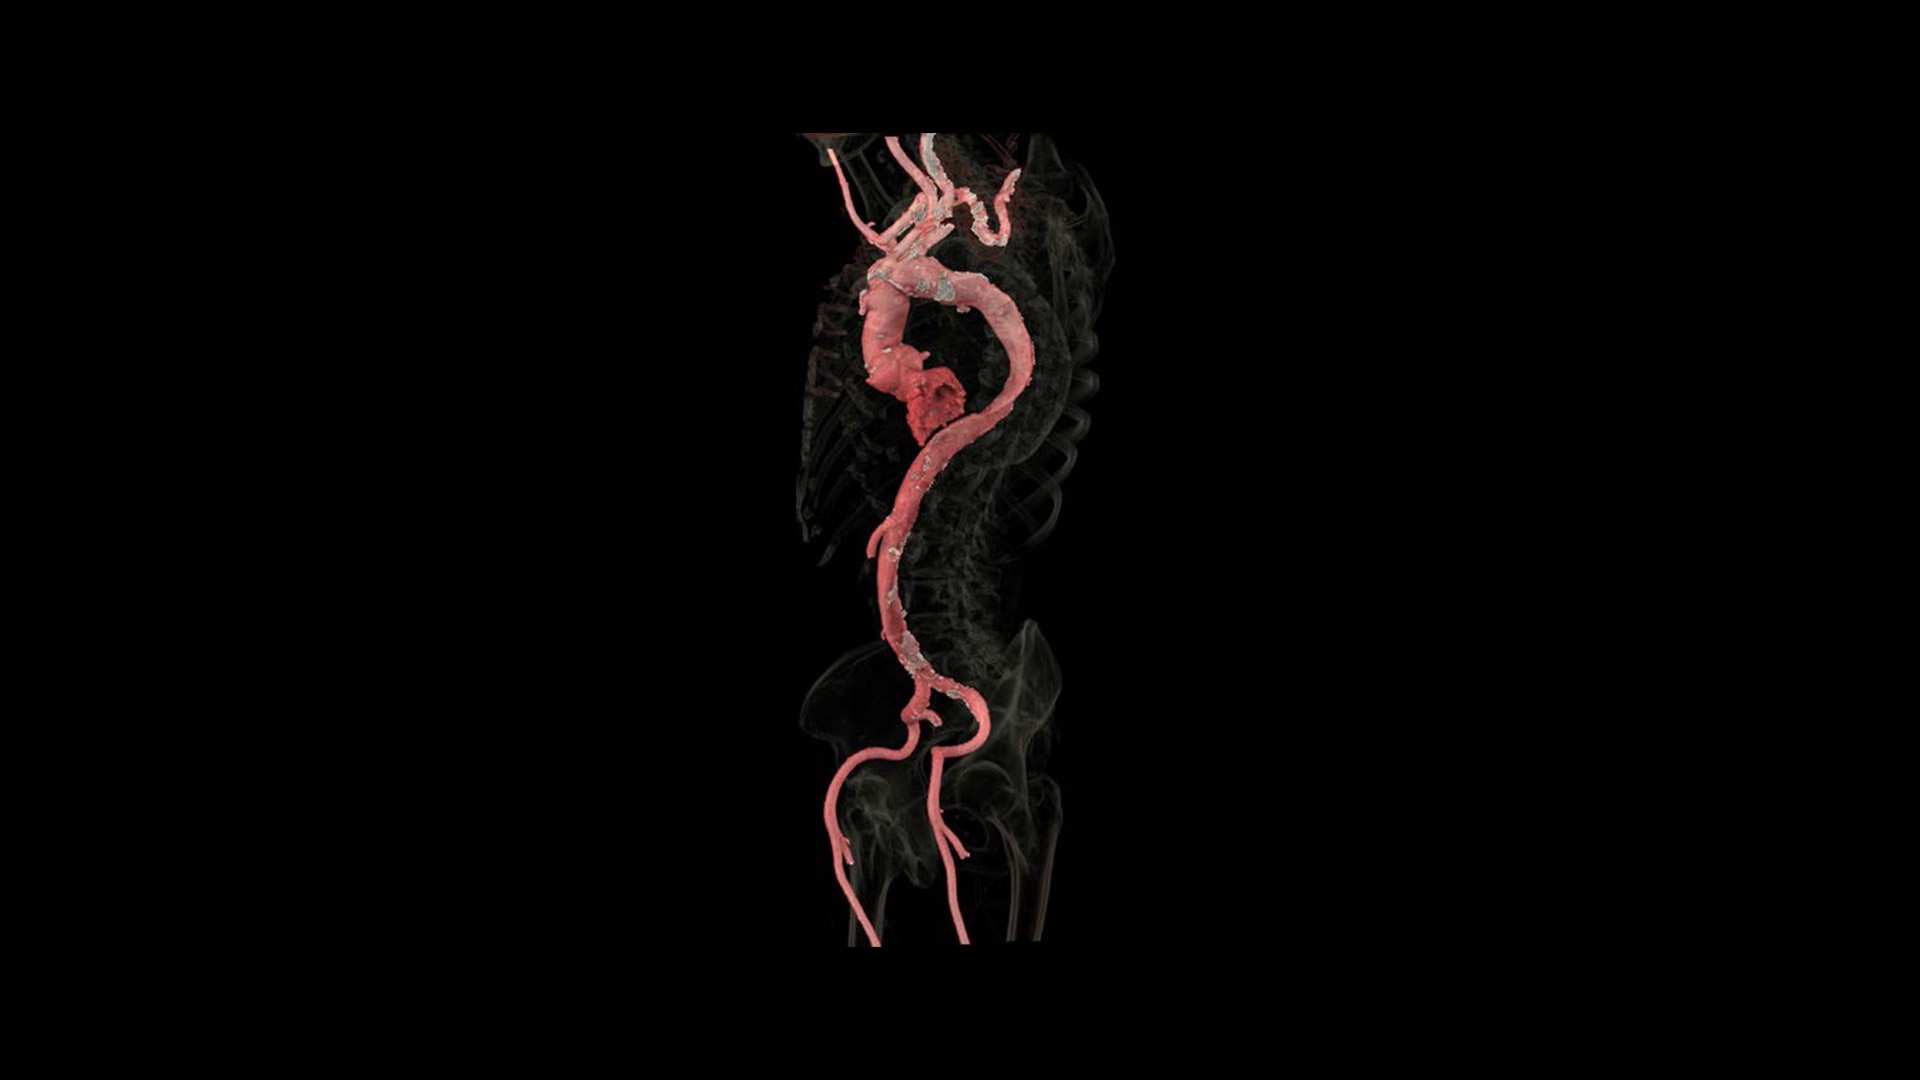

With the Revolution Ascend Platform, you can combine both of our AI-based imaging reconstruction technologies to create one stunning image. By combining True Enhance DL with TrueFidelity DL, you can achieve images that have less noise, enhanced sharpness and better noise texture than images obtained with ASiR-V.

TrueFidelity™ DL is our state-of-the-art image reconstruction technology that uses a DNN to generate high-definition, low-noise CT images. It produces images with exceptional sharpness, low-contrast image quality performance and your preferred noise texture, at the same dose.¹

Available on all Revolution Ascend Platform configurations, Effortless Workflow intelligently automates your CT workflow from pre-scan protocoling to post-scan processing. It uses AI-based features to help transform the entire CT experience and provides maximum efficiency, accuracy, clarity and consistency.

This enables technologists to automatically and accurately personalize scans for each patient with significantly less effort. The end result is a beautiful CT image acquired in less time.